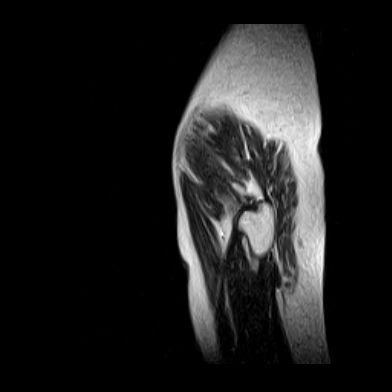

请看看我的片子,我得的什么病,该怎么治疗?谢谢[img][/img]

片子不全,应该是左侧股骨头无菌坏死,右侧似乎没问题,到正规医院治疗,千万别看广告去小医院,吃中药什么的,都是骗人的(说了也白说,百分百都得让人骗点钱才甘心。)

应该是左侧股骨头无菌坏死